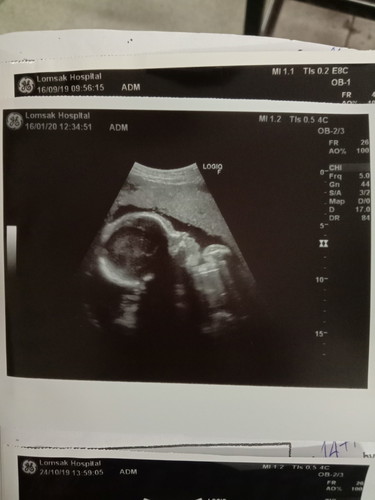

ท้องเราเล็กมากผู้ใหญ่แถวบ้านถามเราว่าทำไมท้องเราเล็ก เหมือนท้องได้ 3-4 เดือน ตอนแรกเราก็กังวลมากกว่าเป็นอันตราย แต่เมื่อวานไปหาหมอมาบอกเราว่าลูกเราน้ำหนักตามเกณฑ์อยู่ ไม่เล็กมาก ไม่ใหญ่มาก กำลังพอดี เรานี้โล่งอกไปเลยค่ะ น้องเป็นผู้หญิงค่ะดิ้นเก่งมาก กำหนดคลอด 22 เมษา ขอดูคุณแม่ที่คลอดเมษาหน่อยค่ะ ?❤️